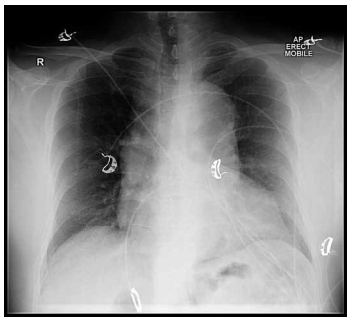

Mulher, 56 anos, portadora de miocardiopatia dilatada não isquêmica e fração de ejeção de 20%, em terapia de ressincronização cardíaca com desfibrilador (CRT-D) implantado há 6 meses, apresenta-se ao consultório com história de 2 semanas de piora progressiva da dispneia aos esforços. Nega qualquer falta de adesão medicamentosa ou dietética. Continua em uso regular dos seguintes medicamentos: furosemida, 40 mg, duas vezes ao dia; carvedilol, 6,25 mg, duas vezes ao dia; sacubitril/valsartana, 24/26 mg, duas vezes ao dia; espironolactona, 12,5 mg ao dia; empagliflozina, 10 mg ao dia.

Ao exame físico: FC 88 bpm; PA 98 x 60 mmHg; pressão venosa jugular 12 cmH2 O; pulmões limpos; ritmo cardíaco regular, com presença de B3; extremidades aquecidas, com leve edema. Realizou eletrocardiograma (ECG), conforme segue:

(Arquivo pessoal; imagem usada com autorização)

A radiografia de tórax mostra leve congestão vascular pulmonar. Assim sendo, assinale a alternativa que a presenta a melhor conduta para esse caso.